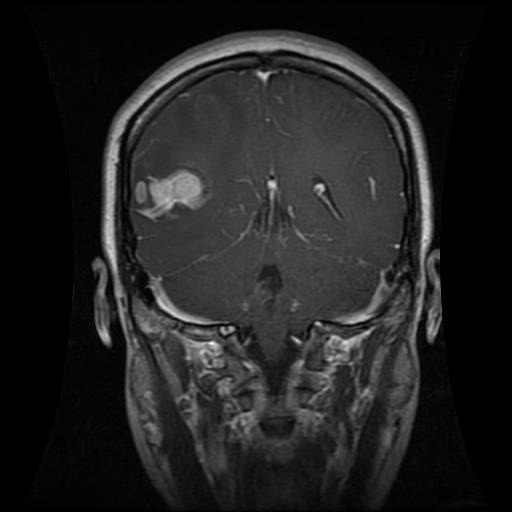

Problem: Radiologists have to spend some time reading brain MRIs and CT scans to find maladies such as a tumor. Currently, neurosurgeons, radiologists, and other medical professionals tend to personally examine hundreds or even thousands of CT scans and MRIs for the presence of brain tumors. This action consumes valuable time that could be used for treatment and other important tasks.

Solution: We created two convolutional neural networks to detect whether an image has a glioma tumor, meningioma tumor, or no tumor at all. Using two AIs mitigates their percent error. They are two very different structures that take in two differently-transformed inputs. Thus, their accuracies should accumulate rather than be the same.